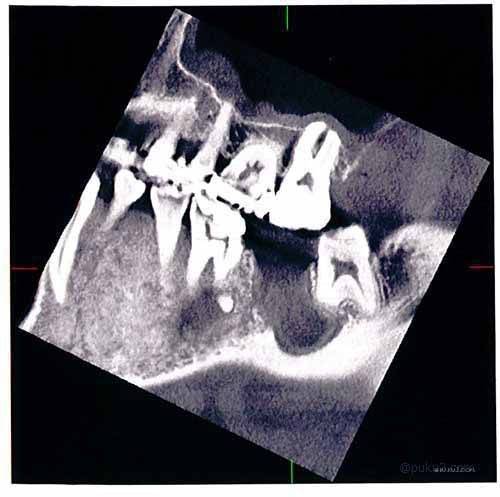

さて、こちらの画像をご覧あれ。

いきなりグロいですかね(笑

虫歯の治療だらけの汚いレントゲン画像ですみません。これが30代半ばのときのキノコ隊長の歯です。Lの字が薄いですが、左の奥歯のところがすっぽり抜けてます。まぁまぁ、虫歯を放置すると年齢関係なくこうなる可能性があるということですね。

そんな左下7番の奥歯を抜歯したあとのレントゲン画像がこちら・・

抜歯した7番を中心に根尖病巣による膿で、歯槽骨が解けているのがわかるかもしれません。6番と8番の歯の影が他とはちょっと違うようにみえるのではないでしょうか。それでも、これだと歯槽骨を溶かしていたということに疑問を抱く方もおりますかね。

そこで、もう一枚みてもらいましょう。

先ほどのレントゲン画像を上から撮ったものを・・

この画像の方が歯槽骨が溶けていることがわかるかもしれません。抜いた7番の歯の空洞はともかく、歯槽骨のラインが思いっきりへこんでおります・・。いやはや怖いですね。

レントゲン画像の入手先

今回の記録帳のレントゲンの画像ですが、これはキノコ隊長自身のものです。よそからの流用などではありません。まぁ、データとして手に入れたものではありませんので、紙に印刷したものをスキャンして画像にしたものです。

この画像の入手先は、今も通う歯医者さんではありません。実は、この歯医者さんの先輩のところです。左下奥歯(7番)を抜歯したあと経過観察をすることになったことは、記録帳内にもあったので覚えているかと思います。経過観察中にこんなことありましたよ。

この機器というのが立体的にレントゲン撮影ができるとうもので、ちょっとスペイシーな感じのするものだったのです。で、その先輩歯医者さんが、

「データ(CD-ROM )は後輩くんに渡してね~、でこっちは印刷したから記念品(笑」

とくださったものです。